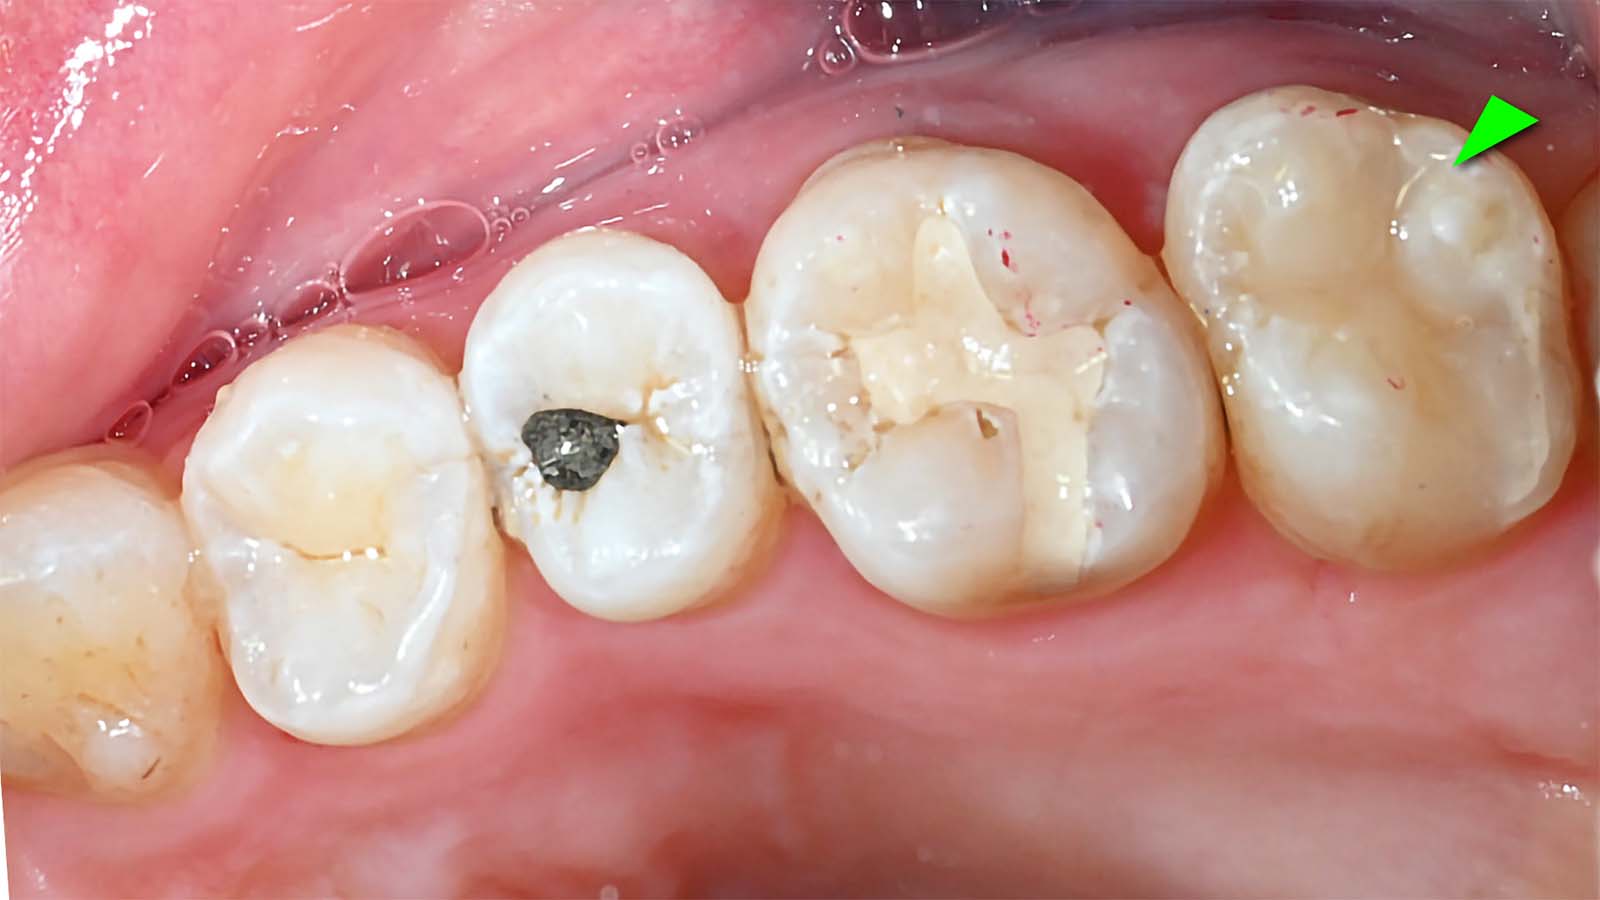

아말감 치료

아말감 사이 치아는 GI로 치료한 결과

오른쪽 아말감 부분에 충치가 생겨서 레진빌드업으로 치료한 결과입니다. 왼쪽부터 아말감, GI, 레진 순서입니다. 아말감은 검고, GI는 치아와 비슷하지만 다르고, 레진은 자연 치아와 구분이 안됩니다.